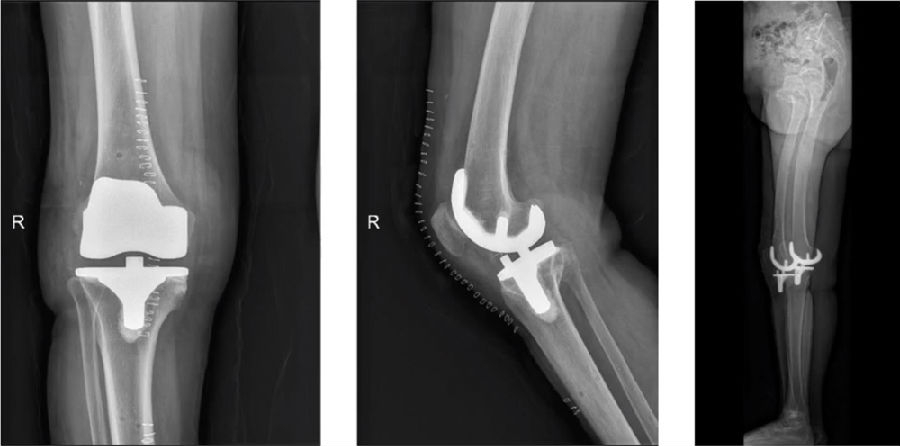

图15 术后影像(R)

图16-17 术后

arKA组术后HKAA、cTCA明显小于aMA组,arKA组cFCA明显大于aMA组,差异均有统计学意义(p<0.05)。

两组术后功能评分均较术前显著改善,不同时间点随访功能结果差异均无统计学意义(p>0.05)。

由此,初步得出结论,导航辅助TKA应用arKA对线的可行性和有效性得到初步证实。该对线技术充分尊重周围软组织,为处理严重膝关节畸形提供了一种新的力线选择,在保护膝关节周围软组织和调控间隙平衡方面更具优势。